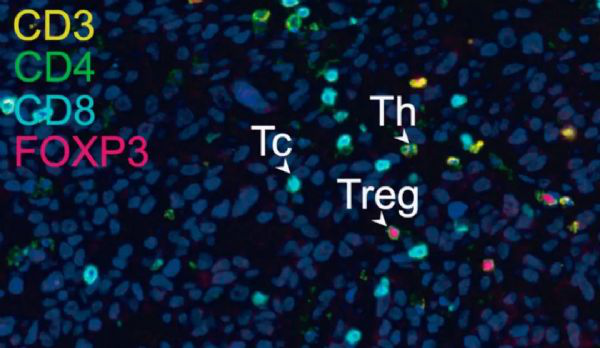

腫瘤組織里面存在多種不同的T細胞

之前的大量研究表明,腫瘤裡面的浸潤T細胞(TILs)是有高度的異質性的。透過實驗研究,Newell團隊也發現肺癌和腸癌患者的腫瘤浸潤性殺傷性T細胞也存在高度的異質性。並不是所有的CD8+ 腫瘤浸潤T細胞都是特異性識別腫瘤表面的抗原的,有些旁觀者 CD8+ 腫瘤浸潤T細胞特異性識別癌症不相關的抗原決定簇。

侵潤T細胞示意圖

總的來說,這個研究證實人體腫瘤組織中不僅有腫瘤特異性的CD8+ 腫瘤浸潤T細胞,還有大量與腫瘤無關的旁觀CD8+ 腫瘤浸潤T細胞。